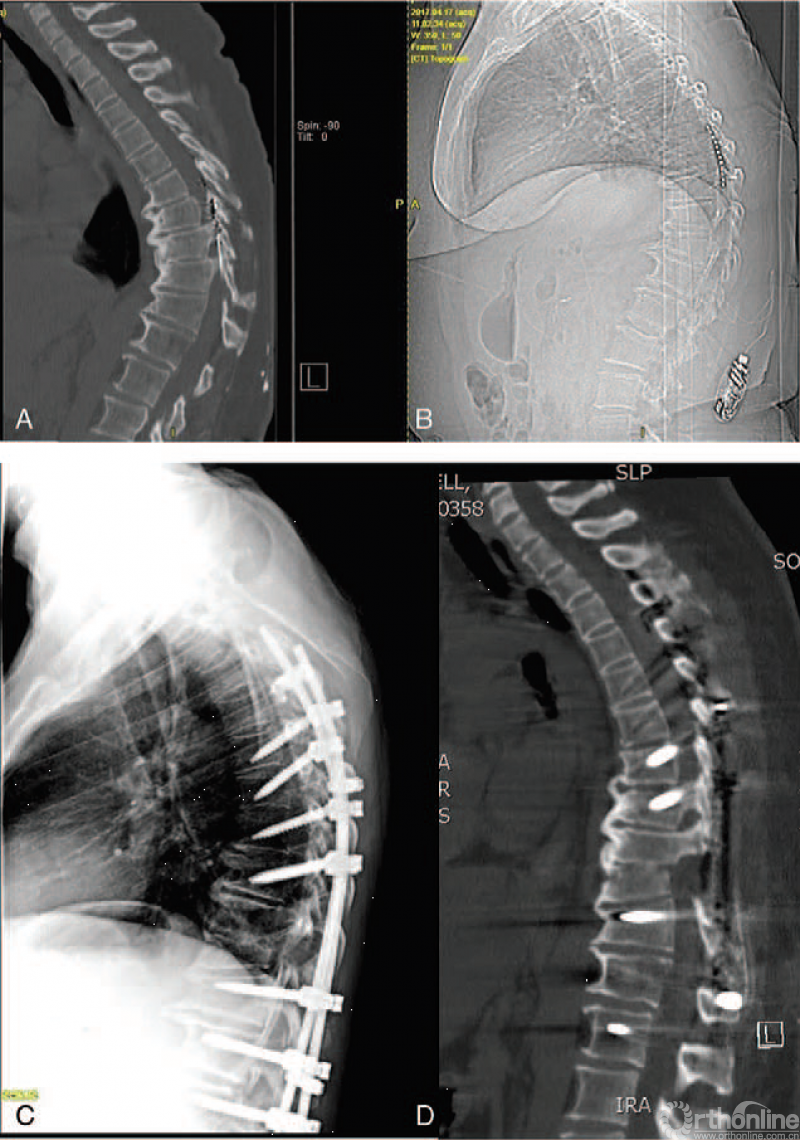

57岁女性,休门氏脊柱后凸畸形(A和B)。脊髓电刺激器不能缓解症状。

取出刺激器,行脊柱截骨术(C、D)后,患者的症状得到很好改善,畸形获得矫正